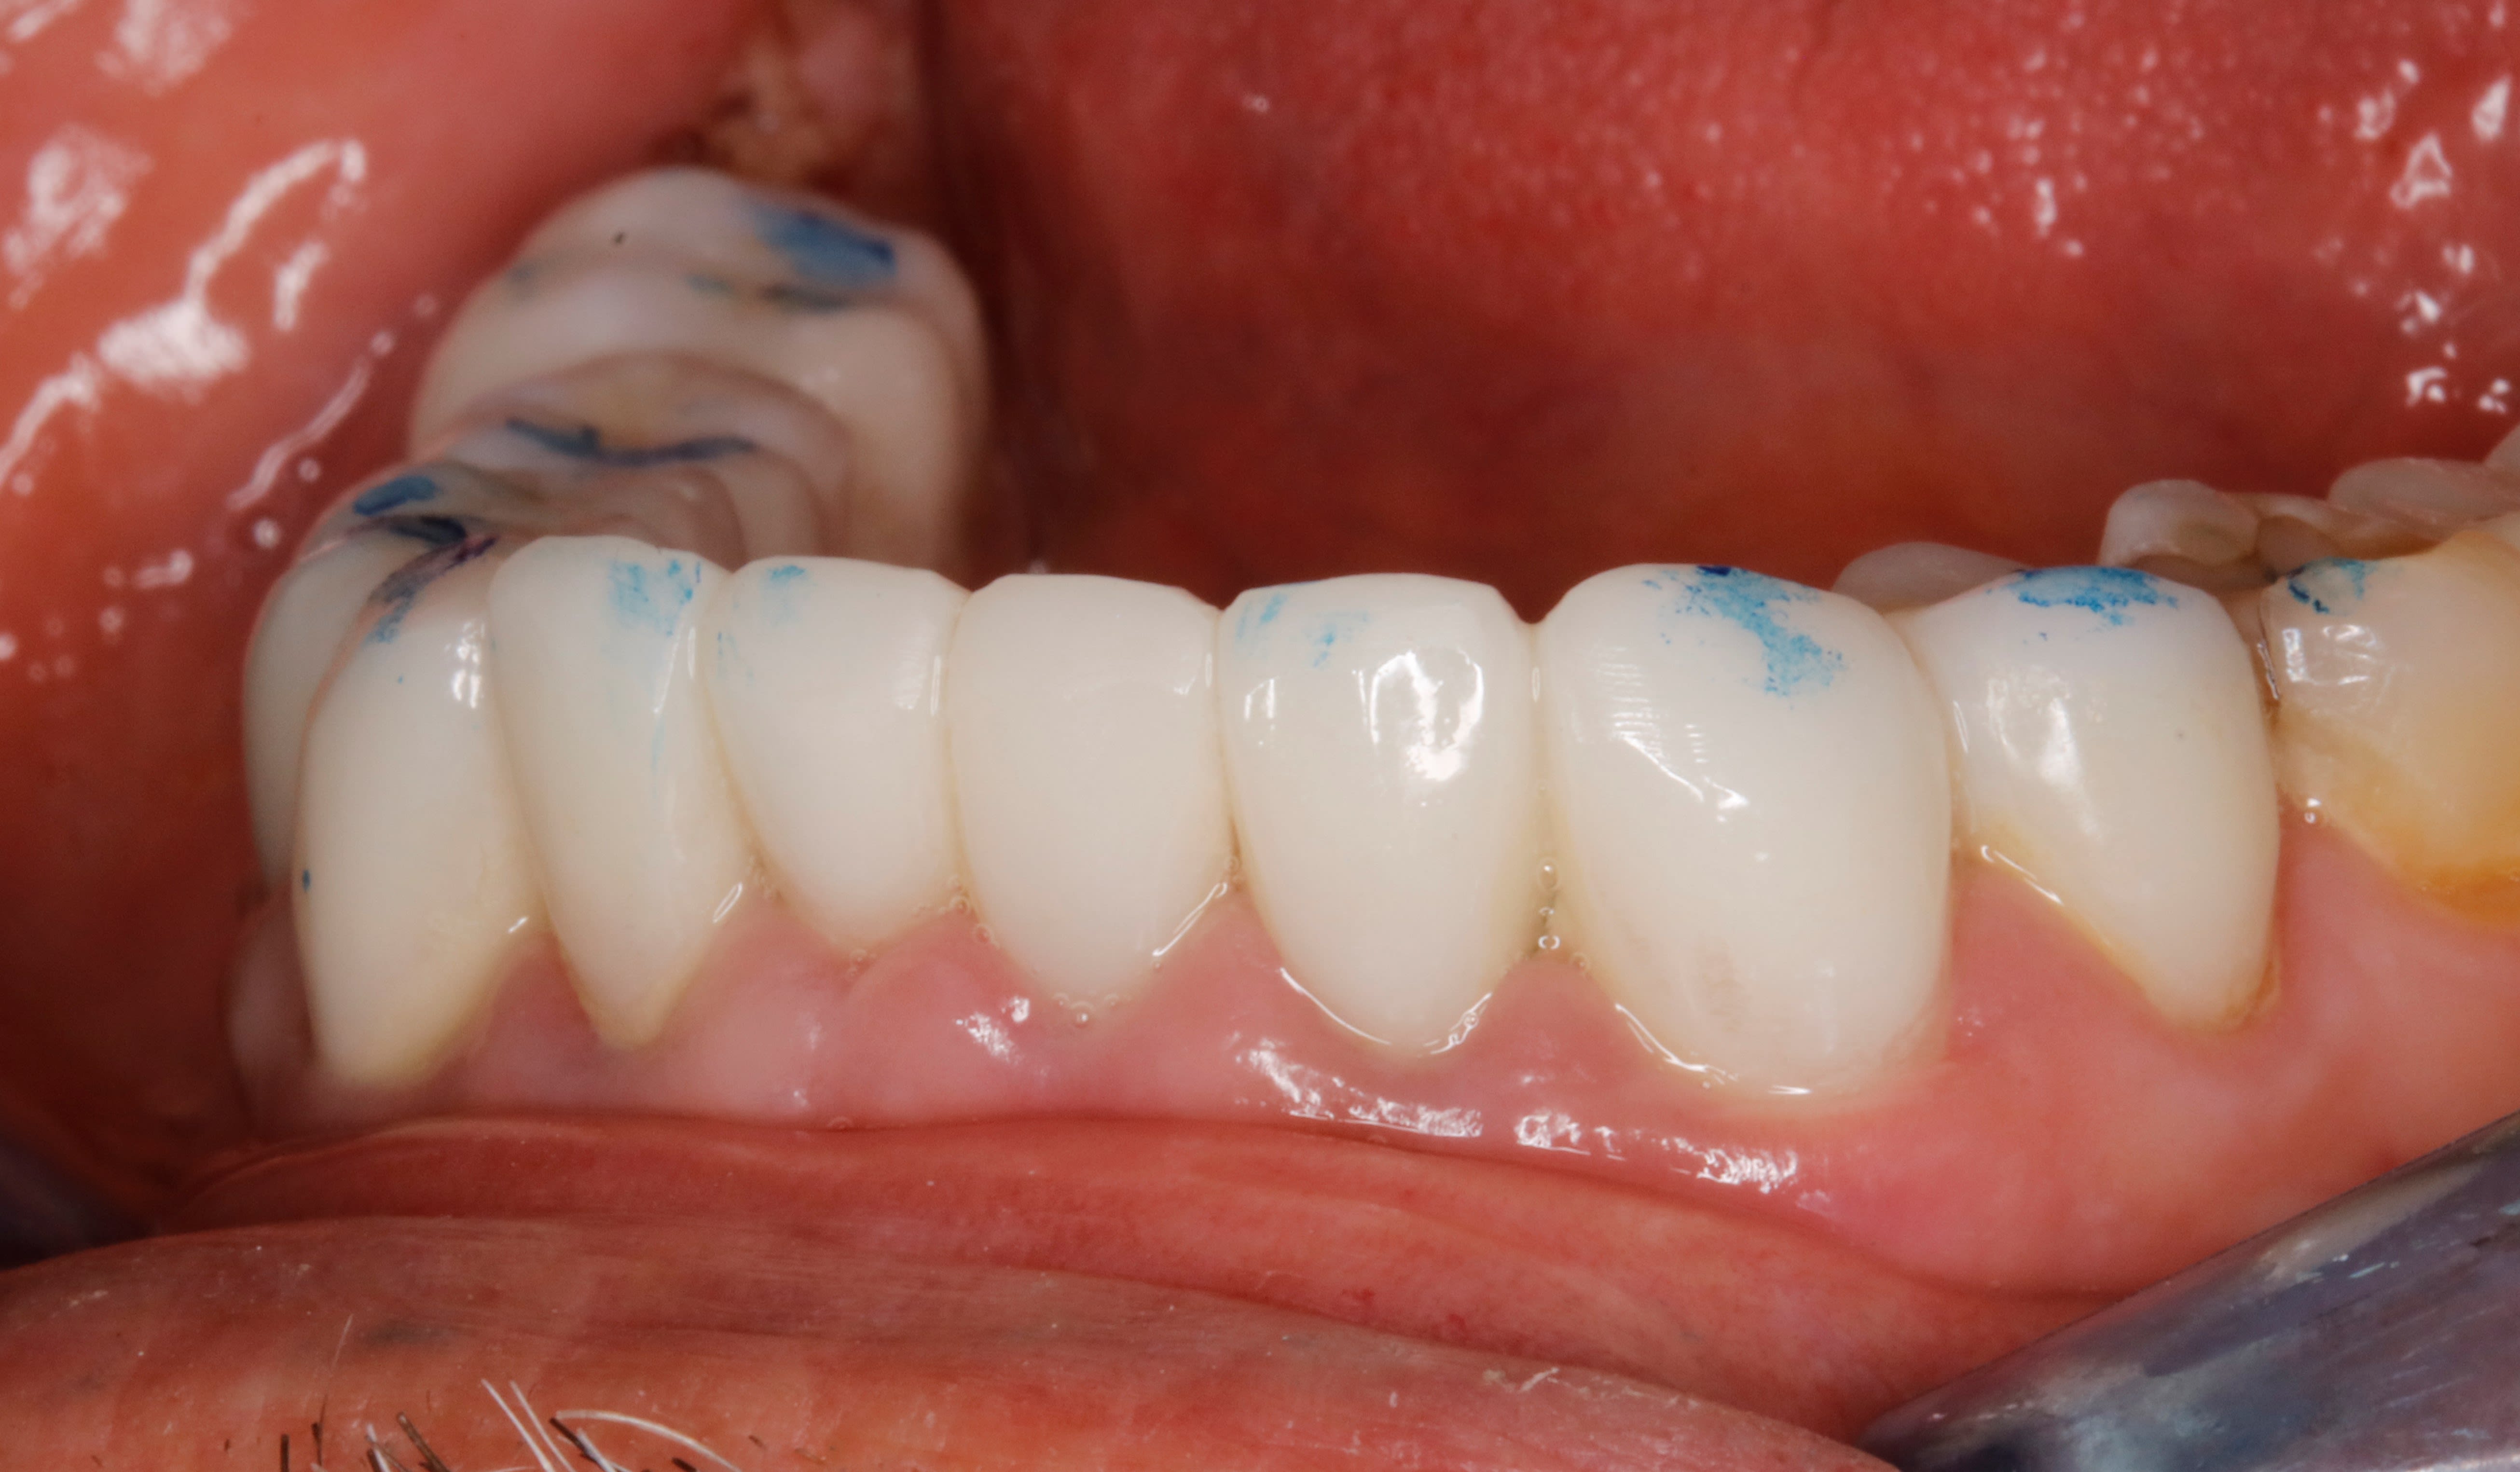

comme ça .

cas n° 3 : dit le coup à la ouane eugaine more

a force de lui recoller ses facettes du bas en urgence , je lui ai conseillé de retourner voir son ricain qui lui a couronné de 33 à 43 .

t as vu comme c est moche ? ses dents du bas sont petitounes en forme de bonbon acidulé en sur occ , trop en arriere , et pour chercher de la rétention ça a été taillé trop profond .

la sur occ + le taillage profond = paro